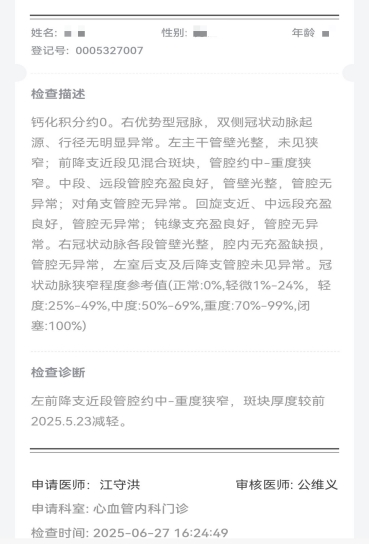

排栓前:左前降支近段管腔约中—重度狭窄 排栓后:到医院检查不符合心脏支架标准